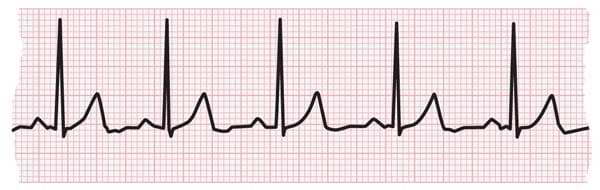

ECG

An electrocardiogram (ECG or EKG) is one of the simplest and fastest tests used to evaluate the heart. Electrodes (small, plastic patches that stick to the skin) are placed at certain spots on the chest, arms, and legs. The electrodes are...